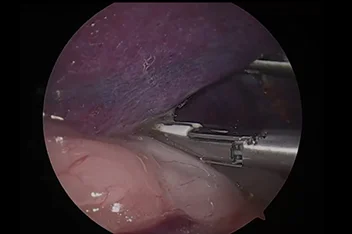

관절경

개,고양이 들은 다양한 관절질환이 존재하고, 복합적으로 존재하는 경우도 빈번합니다.

정확한 진단이 나지 않은 뒤 수술을 하게되면 증상개선이 더디거나 개선이 안될 수 있어, 정확한 진단이 필요합니다.

관절의 경우 X-ray 촬영등으로 진단의 한계가 명확하며, 상위 검사인 CT, MRI 촬영으로도 진단의 한계가 있습니다.

이때 관절경은 내부 구조물들을 직접 시각화 하여 보다 정확한 관절의 상태를 확인하고 진단할 수 있으며, 진단과 치료를 동시에 진행하는 경우도 있습니다. 대표적으로 십자인대단열(CCLR), 골연골염(OCD), 자뼈꿈치돌치유합부전(UAP), 내측관상돌기질환(MCD) 등에 활용될 수있습니다.

관절경 팔꿈치관절(Elbow) 확인

관절경 무릎관절(Stifle) 확인 (반월판 및 십자인대)